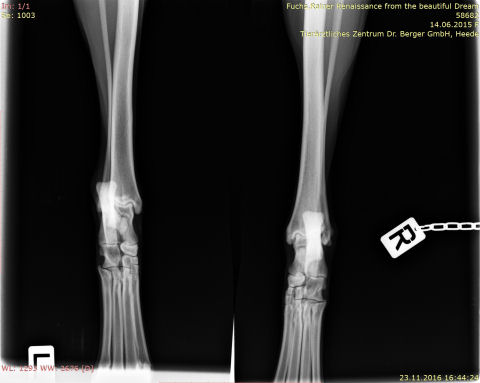

Roxy - OCD

roxy-OCD

IMG-0005-00001-sprunggelenk